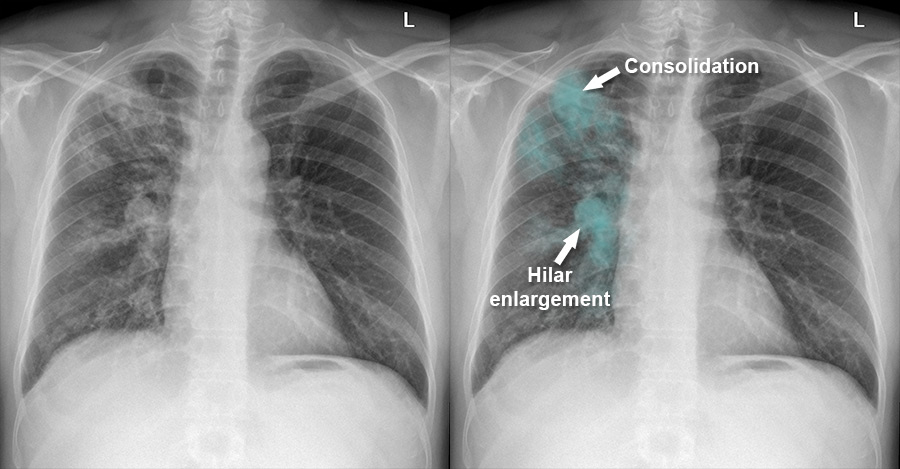

Left middle lobe pneumonia versus normal lung

Comparison of a normal lung and left middle lobe pneumonia

Pneumonia

Feature Description

Consolidation Lobar or segmental increased opacity obscuring lung detail.

Air bronchogram Visible air-filled bronchi within opacified lung parenchyma.

Silhouette sign Loss of normal borders (e.g. heart border, diaphragm) due to adjacent consolidation.